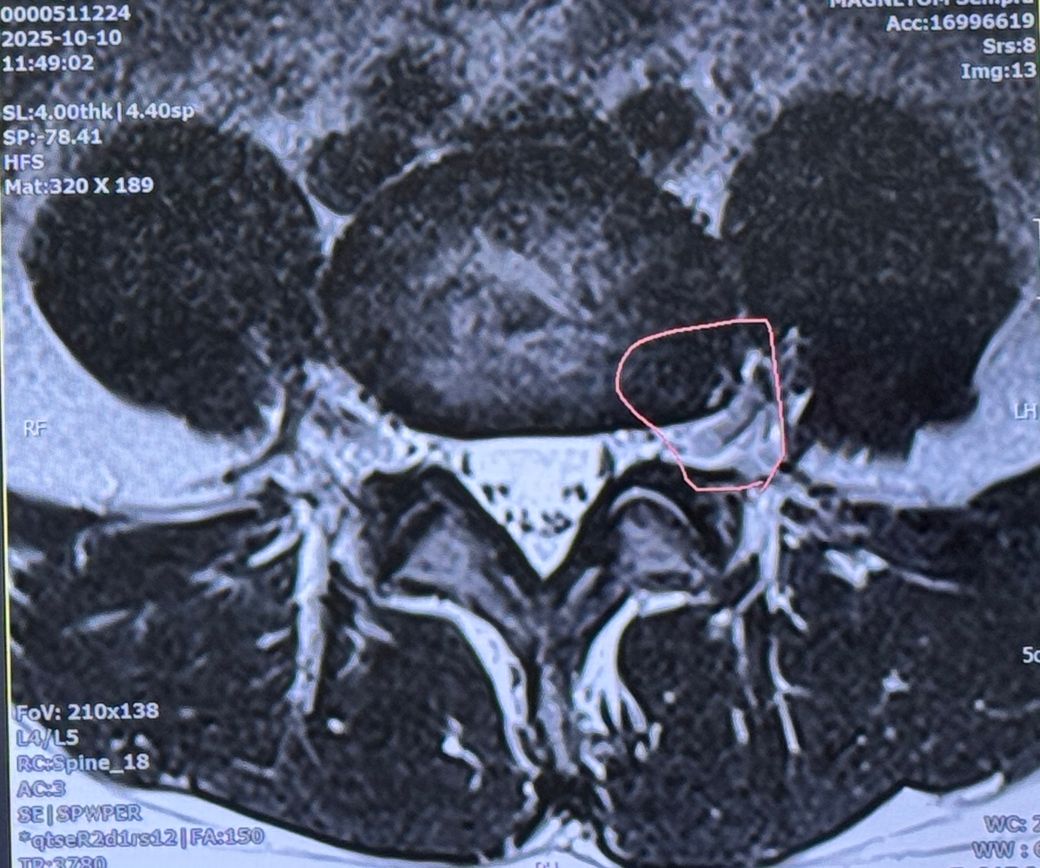

의사쌤 말로는 4-5번 디스크가 터졌다고 하나 수술할 정도나 걱정할 정도는 아니고 그냥 쉬면 된다 하는데 생각보다 방사통이 심합니다..

4번째 사진에서 윗쪽 첫번째 뼈 부근도 혹시 터진건가요? 의사쌤이 따로 말씀은 안하셨는데 궁금해서요.

극외측디스크파열이라고 주변에서 그러던데 그게 희귀하다고 하는데 심각한건가요?

외측디스크파열이라고 의사쌤이 말하진 않았습니다.

• 2번 째 사진